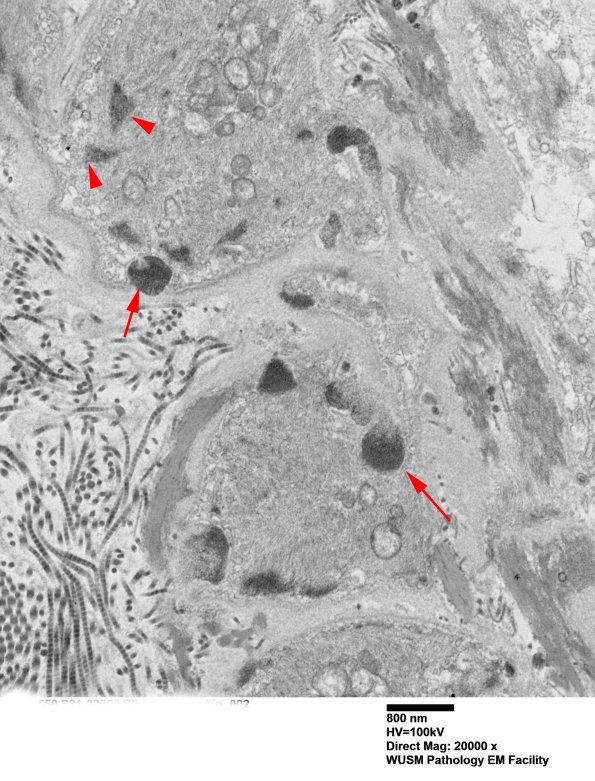

11C1B The vascular smooth muscle contains small normal intracellular filamentous dense bodies (arrowheads) and GOMs (arrow) which are granular and extracellular. Dense bodies are osmiophilic structures in the cytoplasm of smooth muscle cells which are made up of the actin-binding protein α-actinin. (electron micrograph)